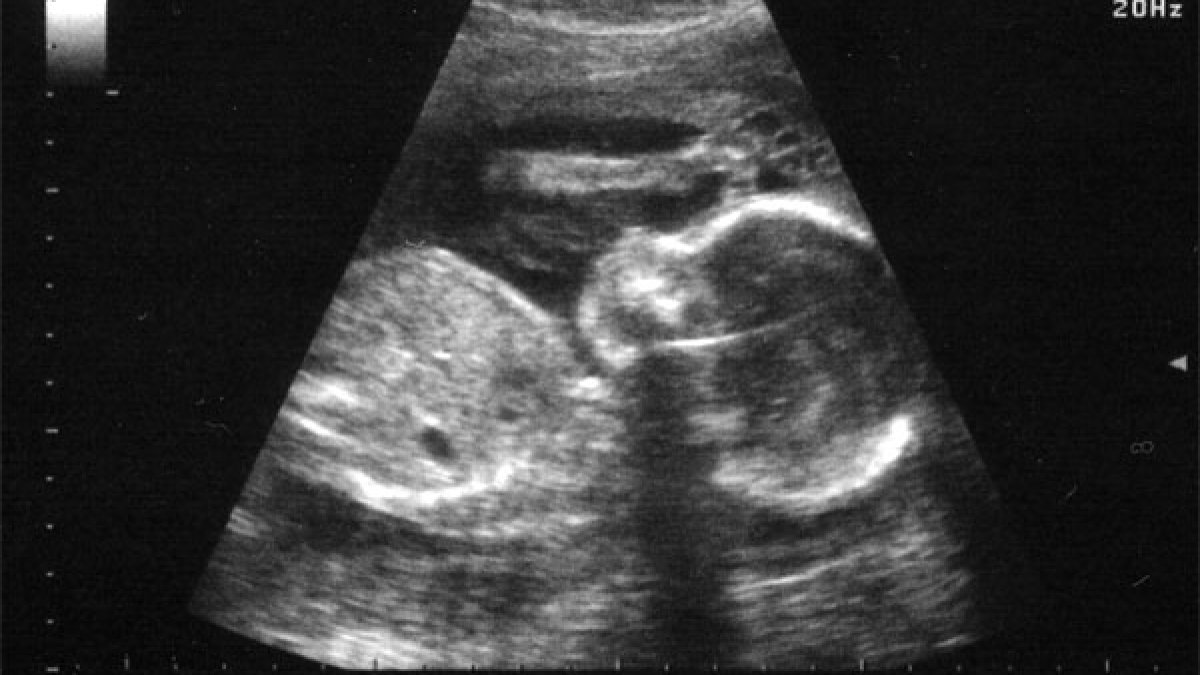

În România, se vorbeşte despre avort. Mai mult sau mai puţin sonoră, fiecare voce care acuză acest act ucigaş contează. Este speranţa unui început curajos de a lăsa viaţa să încolţească, să crească şi să dăinuie. Dacă legea permite, medicul decide În actualul Cod penal, la articolul 199, alineatul 1, litera c, se arată negru pe alb: "Dacă vârsta sarcinii a depăşit paisprezece săptămâni, se pedepseşte cu închisoare de la 6 luni la 3 ani sau cu amendă şi interzicerea exercitării unor drepturi." Ca şi cum n-ar fi fost suficient de clar exprimată legalitatea avortului pe teritoriul românesc, la acelaşi articol din Codul penal, alineatul 6, scrie: "Nu constituie infracţiune avortul terapeutic efectuat de un medic de specialitate obstetrică-ginecologie". Cu toate acestea, în lege însă nu apare o definiţie clară a avortului terapeutic. Cu ce preţ această lipsă de transparenţă legislativă? "Avortul terapeutic rămâne oarecum la bunul plac al medicului. Este o manipulare lingvistică grosolană. Este o terminologie ipocrită folosită în ultimii 20, 30 de ani ca să mai îndulcească, să zic aşa, terminologia referitoare la avort. Relaţia tradiţională, de când există profesia de medic, între doctor şi pacient este una de tip taumaturgic, adică pacientul se duce la medic, şi acesta din urmă, dacă poate, bineînţeles, îl vindecă. Or, noi ce avem în situaţia aceasta? Avem două persoane sănătoase, mama şi copilul, care merg la medic şi de acolo se întoarce doar una, mama, care rămâne bolnavă, traumatizată pe tot restul vieţii, iar cealaltă persoană este omorâtă", spune Bogdan I. Stanciu, preşedintele filialei din Bucureşti a Asociaţiei "Pro-vita pentru născuţi şi nenăscuţi". Ce este avortul terapeutic "Din punct de vedere medical, avem de-a face cu un avort terapeutic în cazul în care sarcina pune în pericol iminent viaţa femeii, deci pericolul este real, şi acest pericol nu poate fi înlăturat decât prin avort. În România, aceasta este definiţia, acceptată de colegii mei din subcomisie. Avortul terapeutic nu înseamnă că fătul are o malformaţie. Sarcina nu este o boală. Spre exemplu, avem o femeie care poartă o sarcină, are nevoie de un transplant de cord, iar pericolul în care este femeia este unul iminent. Dacă mai continuă sarcina, ea moare. În aceste condiţii trebuie să alegi: mor amândoi sau moare numai unul", declară prof. dr. Vasile Astărăstoaie, preşedintele Colegiului Medicilor din România şi al Societăţii Române de Bioetică. De asemenea, profesorul Astărăstoaie invocă Codul deontologic al medicilor, unde apare "dreptul la conştiinţă", valabil pentru acei doctori care, datorită concepţiilor lor religioase, nu vor să facă o serie de activităţi medicale. Astfel, ei au dreptul să îşi exercite profesia după cum le dictează propria conştiinţă, bineînţeles, în limitele legale, cu o singură condiţie: să nu abandoneze pacientul, pentru că altfel sunt culpabili că l-au lăsat să moară. Malformaţiile incompatibile cu viaţa Prof. dr. Bogdan Marinescu, medic primar obstetrică-ginecologie, directorul Maternităţii Giuleşti din Bucureşti, duce mai departe discuţia: "Luăm exemplul unui copil fără cap. Nu are sens să laşi mama să se chinuiască până la termen pentru a naşte un copil care nu are nici o şansă de supravieţuire. Este vorba aici de malformaţiile incompatibile cu viaţa. Că se discută dreptul mamei de a hotărî asupra produsului de concepţie pentru nişte malformaţii care nu sunt incompatibile cu viaţa (faptul că îi lipsesc unul sau două degete, sau o mână, asta nu îl împiedică să se dezvolte, să aibă o minte brici, şi să devină ulterior şef de companie sau director de bancă) este, din punctul meu de vedere, incorect. Acest drept al mamei asupra vieţii copilului, iarăşi spun, din punctul meu de vedere, se pune sub semnul întrebării. De ce? Pentru că aceste malformaţii, de regulă, sunt depistate la o vârstă înaintată, la 30, 32, 34 de săptămâni, unde, chiar întreruptă sarcina, fătul trăieşte. Ce poţi să-i faci? O declanşare de travaliu sau să-l extragi prin operaţie cezariană, ceea ce nu e cel mai corect lucru. După aceea, ce faci cu el? Îl dai cu capul de pământ? Nu se poate." "Nu hotărăşte medicul, ci Dumnezeu" "Cine dă doctorului dreptul să fie Dumnezeu? Să hotărască el ziua, ora, când, cum, când se termină şi de ce se termină?", întreabă retoric Carmen Georgescu, medic primar obstetrică-ginecologie de la Maternitatea Giuleşti din Capitală. Doamna doctor, o creştină, este cunoscută în maternitate ca fiind îngerul copiilor, deoarece în cabinetul dumneaei intră doar femeile care doresc să aducă pe lume copii. Medicul Georgescu vorbeşte cu dragoste despre mogâldeţele pe care le întâmpină zâmbitoare în pragul vieţii. Crede în Dumnezeu şi în pronia Lui. Luca este doar un exemplu al Existenţei darnice. La doar 27 de săptămâni, medicii au hotărât să-l scoată pe Luca din pântecele mamei, căreia îi punea în pericol viaţa, mai mult, copilul era suferind. Cu toate acestea, micuţul s-a încăpăţânat să trăiască. Aşa se face că anul trecut, în Vinerea Mare, doamna doctor Carmen Georgescu căuta cu sufletul răvăşit un preot să-i boteze puiul. L-a găsit, după îndelungi căutări. A fost bine. Astăzi, Luca trăieşte. "Nu decid eu, medicul, ce viaţă are copilul acela. Dacă Dumnezeu vrea să se stingă în pântecele mamei lui, aşa va fi, că El ştie ce face. O încearcă pe mamă, îi dă frica, îi dă durerea, şi până la urmă se duce. Copilul moare, şi-l avortează. Dar nu hotărăşte medicul, ci Dumnezeu. Eu nu zic că cel pe care îl văd la ecograf că are ceva va trăi, dar Dumnezeu hotărăşte când îl scoate. Poate Cel de Sus vrea să o mângâie pe mamă, care doreşte să-şi vadă copilul, să-i sufle de două ori, să-l boteze apoi, şi ea să fie mângâiată în felul acesta", conchide medicul Carmen Georgescu. Umbrele răului Chiar dacă poate părea pentru unii obsesiv, repet: în România, se vorbeşte despre avort. Mai mult sau mai puţin sonoră, fiecare voce care acuză acest act ucigaş contează. Şi adaug, vocile care se fac auzite sunt speranţa unui început curajos de a lăsa viaţa să încolţească, să crească şi să dăinuie. Cum de la dorinţă la realitate este cale lungă - mai ales când vine vorba de un sistem socio-politic ca al nostru, servit cu devotament de cei mai întunecaţi discipoli ai răului -, noi, ceilalţi, nu putem decât să ne lăsăm "otrăviţi" în fiecare zi de chinul propriei conştiinţe, încă trează, care arată cu degetul spre umbrele (multe dintre ele cu chip uman) care frâng vieţi.